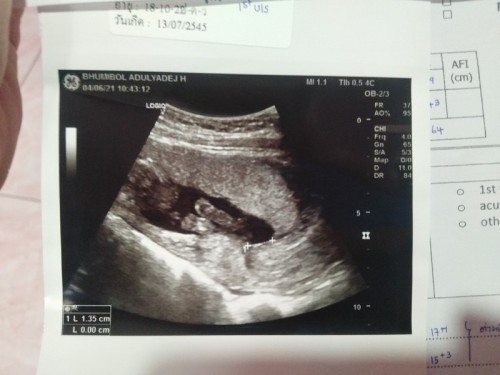

เป็นหน้าแข้ง2ข้างค่ะ น้องหันหน้าออก น้องหนีบขาไว้ค่ะ ต่อให้น้องอ้าขา ก็คงมองไม่ออก เพราะต้องมองจากมุมก้นขึ้นไปหาหัวค่ะ

เห็นเหมือนเท้าน้องเลยค่ะ เรื่องเพศต้องให้คุณหมอบอกค่ะแม่ คนอื่นที่ไม่ใช่หมอตอบไม่ได้แน่นอน

น่าจะเป็นเท้า ไม่เห็นเพศค่ะ